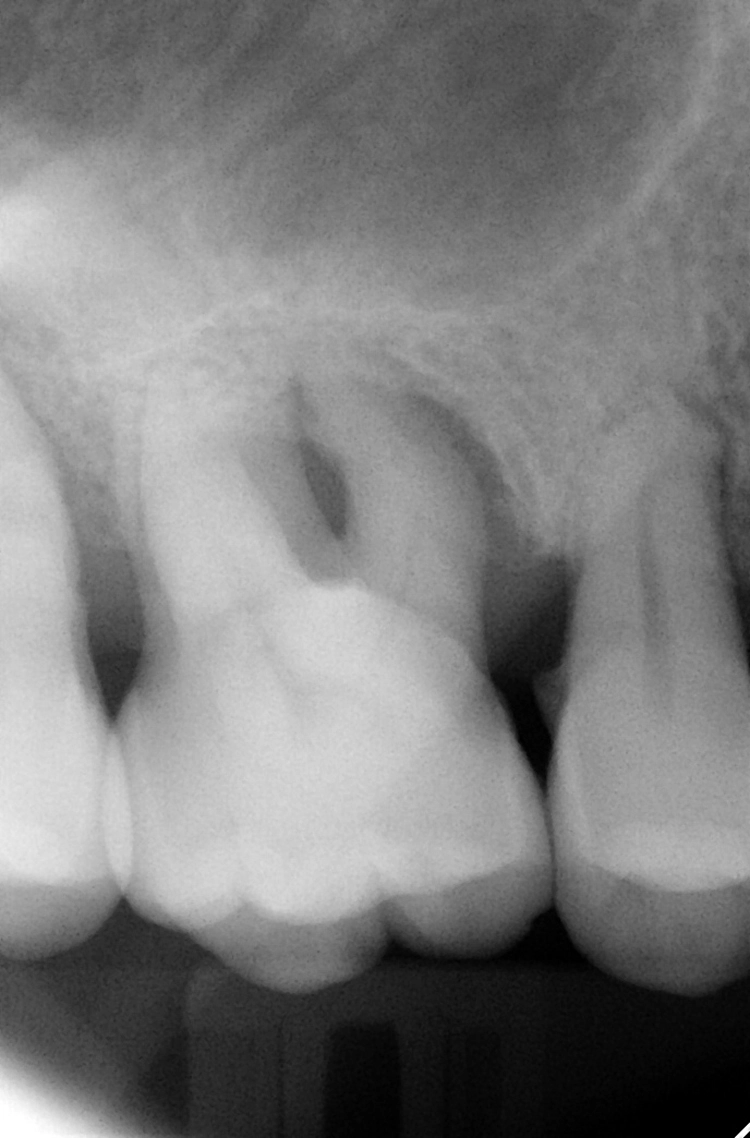

Mit dem primärstabilen WS-Condenser ø 4,3 mm wurde eine radiologische Messaufnahme durchgeführt. Dieser Fall wurde durch die neu geschaffene Kavität der IDS (interner, direkter Sinuslift) mit Smart Grinder-Material und dem im OP-Tray enthaltenen Ricci II-Instrument durchgeführt.

Gleich im Anschluss wurde ein CHAMPION (R)Evolution L 8 mm | ø 4,5 mm – ebenfalls im MIMI-Verfahren – mit einer Primärstabilität von 40 Ncm inseriert. Das DVT zeigt sehr deutlich die „weiße Wolke“ des Grinder-Materials, welches mehr Knochenwachstumsfaktoren enthält als Knochen selbst und durch die Schneider‘sche Membran optimal ernährt wird. Am gleichen Operationstag erfolgte die geschlossene Abformung samt Bissnahme (Abb. 20-23).